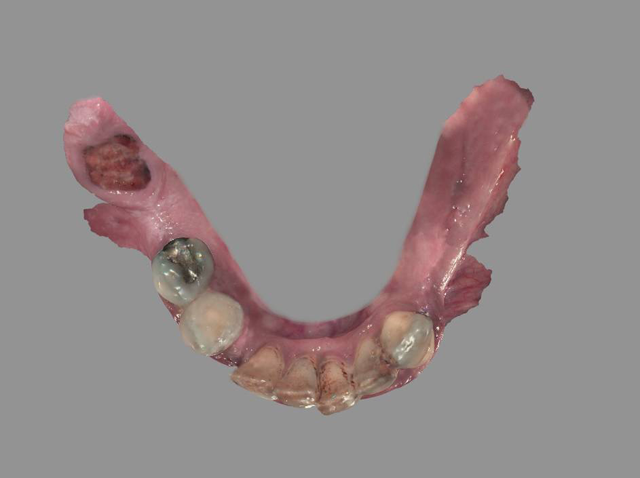

After extracting the mandibular teeth (Figs. 7 & 8), the ridge was leveled in the same manner as the maxillary arch. However, four 4x12 mm Engage™ (OCO Biomedical) dental implants (Fig. 9) were placed in key positions to support overdenture prosthesis. These implants were used because their design offers high initial stability for selective loading options due to their patented Bull Nose Auger™ tip and Mini Cortic-O Thread™. Tall healing caps of 5 mm (OCO Biomedical) were placed onto the dental implants so that they would extend through the tissue once sutured and aid in supporting the lower immediate denture.

Fig. 9 Fig. 10